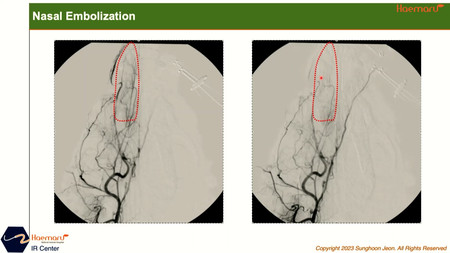

연이어 진행된 인터벤션센터 전성훈 센터장은 비강 종양의 영상의학적 특징 소개 및 해마루 인터벤션 센터의 최근 증례들에 대해 다루었다. 해마루 동물병원 인터벤션센터는 현재까지 약 200건의 인터벤션 시술을 해왔으며, 그 중 비강종양 색전술의 기본원리와 증례에 대해서 소개하였다. 최근 1년간 비강 색전술을 진행한 환자 11마리의 시술 전후 치료 반응을 발표하였으며, 시술 후 1개월에 촬영한 CT 영상을 기준으로 10/11마리에서 임상적 유용성(clinical benefit)이 확인되었다. 특히 1마리에서 완전 관해 (CR), 7마리에서 부분 관해 (PR) 의 변화를 보였으며, 대부분의 환자에서 기존 방사선 치료 대비 상대적으로 저렴한 비용과 적은 횟수의 마취로 단기간 임상증상을 완화시키는 변화를 보여 좋은 치료방법이 될 수 있는 것으로 확인되었다.